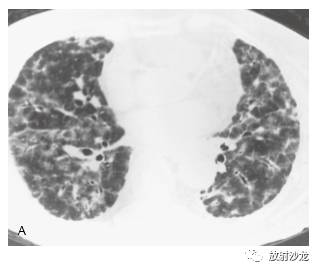

磨玻璃影是一个非特异性术语,指HRCT上 肺密度模糊地增高,这有些随意性。它不掩蔽其 中的血管或支气管边缘(图 5-1 ~图 5-3),如果血管影被掩蔽了一般使用术语“实变”。该 表现反映多种异常,可见于气腔病变(图 5-3), 间质增厚(图 5-4),部分肺泡萎陷(肺不张), 毛细血管容量增加,或它们的组合。

如磨玻璃影很轻微或弥漫分布,程度一致的累及全肺,则辨认困难。但磨玻璃影几乎总是呈片状分布,累及有些肺区,而不累及其他肺区。 这种肺实质的“地图样”表现很容易有信心地检 出和诊断(图5-3,图5-5)。在有些病例中,整 个肺小叶表现为异常致密,而邻近肺小叶正常。另一些病例的磨玻璃影呈小叶中心性和支气管周 围分布,形成边缘不清的小叶中心性结节。磨玻璃影可累及个别肺段和肺叶,也可累及不按肺段的肺区(图 5-6),或是弥漫的(图 5-7)。在肺区内出现表现“过黑”的含气支气管 也是有磨玻璃影的线索,这种黑色支气管表现本 质上是空气支气管征。